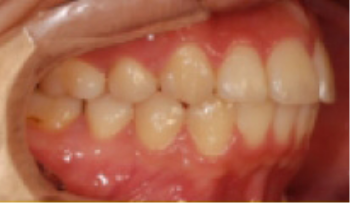

• 총생(Crowding) 치아가 삐뚤게 남.

Before

After